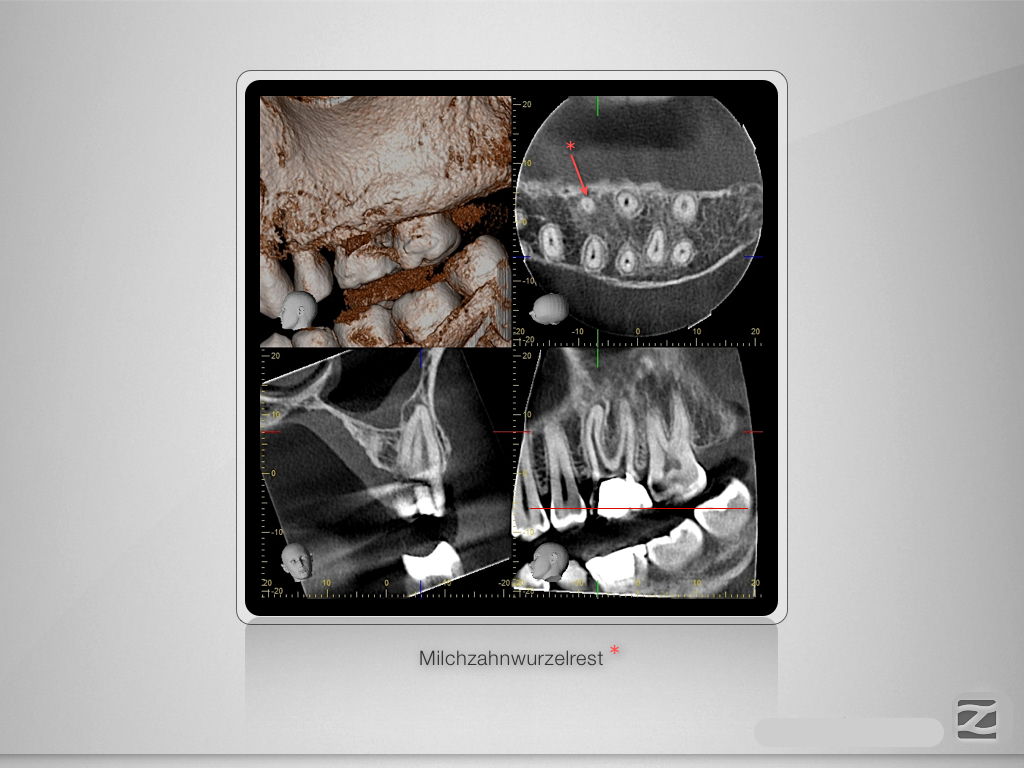

26D.006

Entwarnung